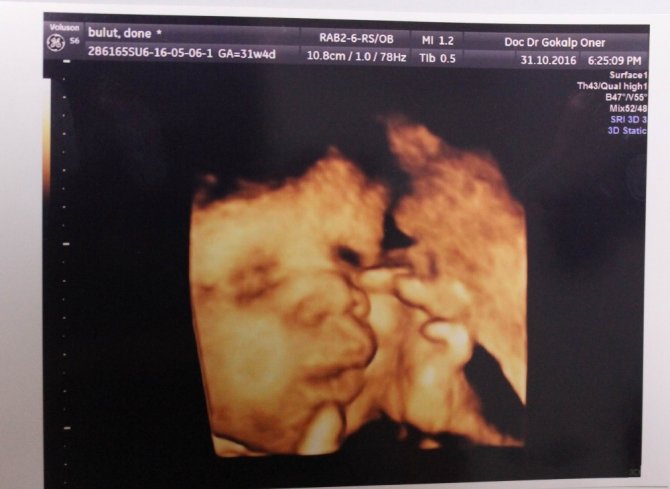

Anne karnındaki bebeklerin çekildiği dört boyutlu ultrason fotoğraflara takılan pozlar bazen şaşırtıyor. Henüz 22 haftalıkken zafer işareti yapan bebeğin fotoğrafı bunlardan en ilgi çekici olanı.

Memorial Kayseri Hastanesi Kadın Hastalıkları ve Doğum Uzmanı Doç. Dr. Gökalp Öner'in yaklaşık 2 yıldır çektiği 400'ün üzerinde, dört boyutlu ultrason fotoğraflara takılan anne karnındaki bebeklerin ilginç pozları dikkat çekiyor. Zafer işareti yapan, burnunu karıştıran, dilini çıkaran, uzun hava çeken, düşünen bebek fotoğrafları ebeveynleri hem mutlu ediyor hem de şaşkınlığa uğratıyor.

Mutlu geçirilmesi gereken hamilelik dönemini bu fotoğraflarla renklendirdiklerini dile getiren Doç. Dr. Gökalp Öner, "Bu fotoğraflarda bazen ilginç pozlar yakalıyoruz. Bebeklerimiz ağlarken, gülerken, düşünürken, zafer işareti yaparken, burnunu karıştırırken... Bunları yakaladığımızda ailenin de bizim de hoşumuza gidiyor. Böyle mutlu anları paylaşıyoruz. Çünkü gebelik süreci ve doğum, düğün gibi mutlu geçirilmesi gereken bir süreç" ifadelerini kullandı.